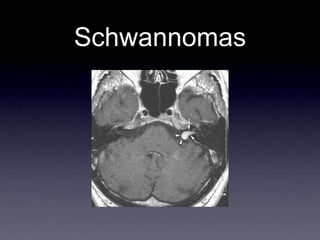

Schwannomas